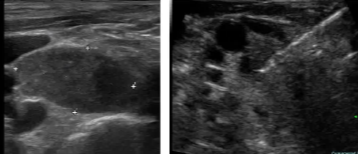

术前手术甲状腺切除术,放射性碘难治性和局部复发累及的DTC 患者采用超声引导下的RFA治疗

建议13-14:淋巴结复发的治疗既往手术甲状腺切除术,放射性碘难治性和淋巴结复发累及的DTC患者采用超声引导下的RFA治疗

甲状腺癌复发消融

复发性甲状腺滤泡癌,累及气管